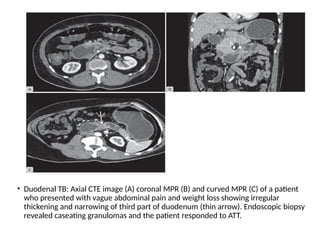

Duodenal Tuberculosis

• It constitutes only about 2% of all GI TB.

• CT may show thickening of the duodenal wall commonly

involving the second and the third part, which may be

associated with stricture and proximal dilatation.

• Duodenal TB can mimic CD, lymphoma and carcinoma

and it is usually difficult to differentiate them. Biopsy is

confirmatory for the diagnosis.

• Duodenal TB: Axial CTE image (A) coronal MPR (B) and curved MPR (C) of a patient

who presented with vague abdominal pain and weight loss showing irregular

thickening and narrowing of third part of duodenum (thin arrow). Endoscopic biopsy

revealed caseating granulomas and the patient responded to ATT.

Duodenal Tuberculosis • Itconstitutes only about 2% of all GI TB. • CT may show thickening of the duodenal wall commonly involving the second and the third part, which may be associated with stricture and proximal dilatation. • Duodenal TB can mimic CD, lymphoma and carcinoma and it is usually difficult to differentiate them. Biopsy is confirmatory for the diagnosis.

• Duodenal TB:Axial CTE image (A) coronal MPR (B) and curved MPR (C) of a patient who presented with vague abdominal pain and weight loss showing irregular thickening and narrowing of third part of duodenum (thin arrow). Endoscopic biopsy revealed caseating granulomas and the patient responded to ATT.